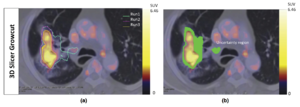

- 1.85 Hybrid Positron Emission Tomography Segmentation of Heterogeneous Lung Tumors using 3D Slicer: Improved Growcut Algorithm with Threshold Initialization

- 1.86 Pre-clinical Validation of Virtual Bronchoscopy using 3D Slicer